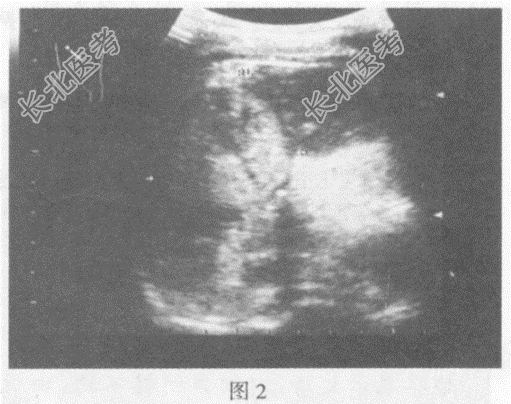

- 单项选择题临床资料:女性患者, 35岁,自述右上腹胀痛, 食欲不振。Casoni试验阳性。患者生活于牧区。

图1: 肝右叶可见7.4cm×6.3cm无回声区,包膜完整, 可见双层强回声壁,厚度不均, 且可见强回声突起,后方声加强, 无回声内另可见细小中等回声光点及膜状回声随体位变动而自由漂浮。